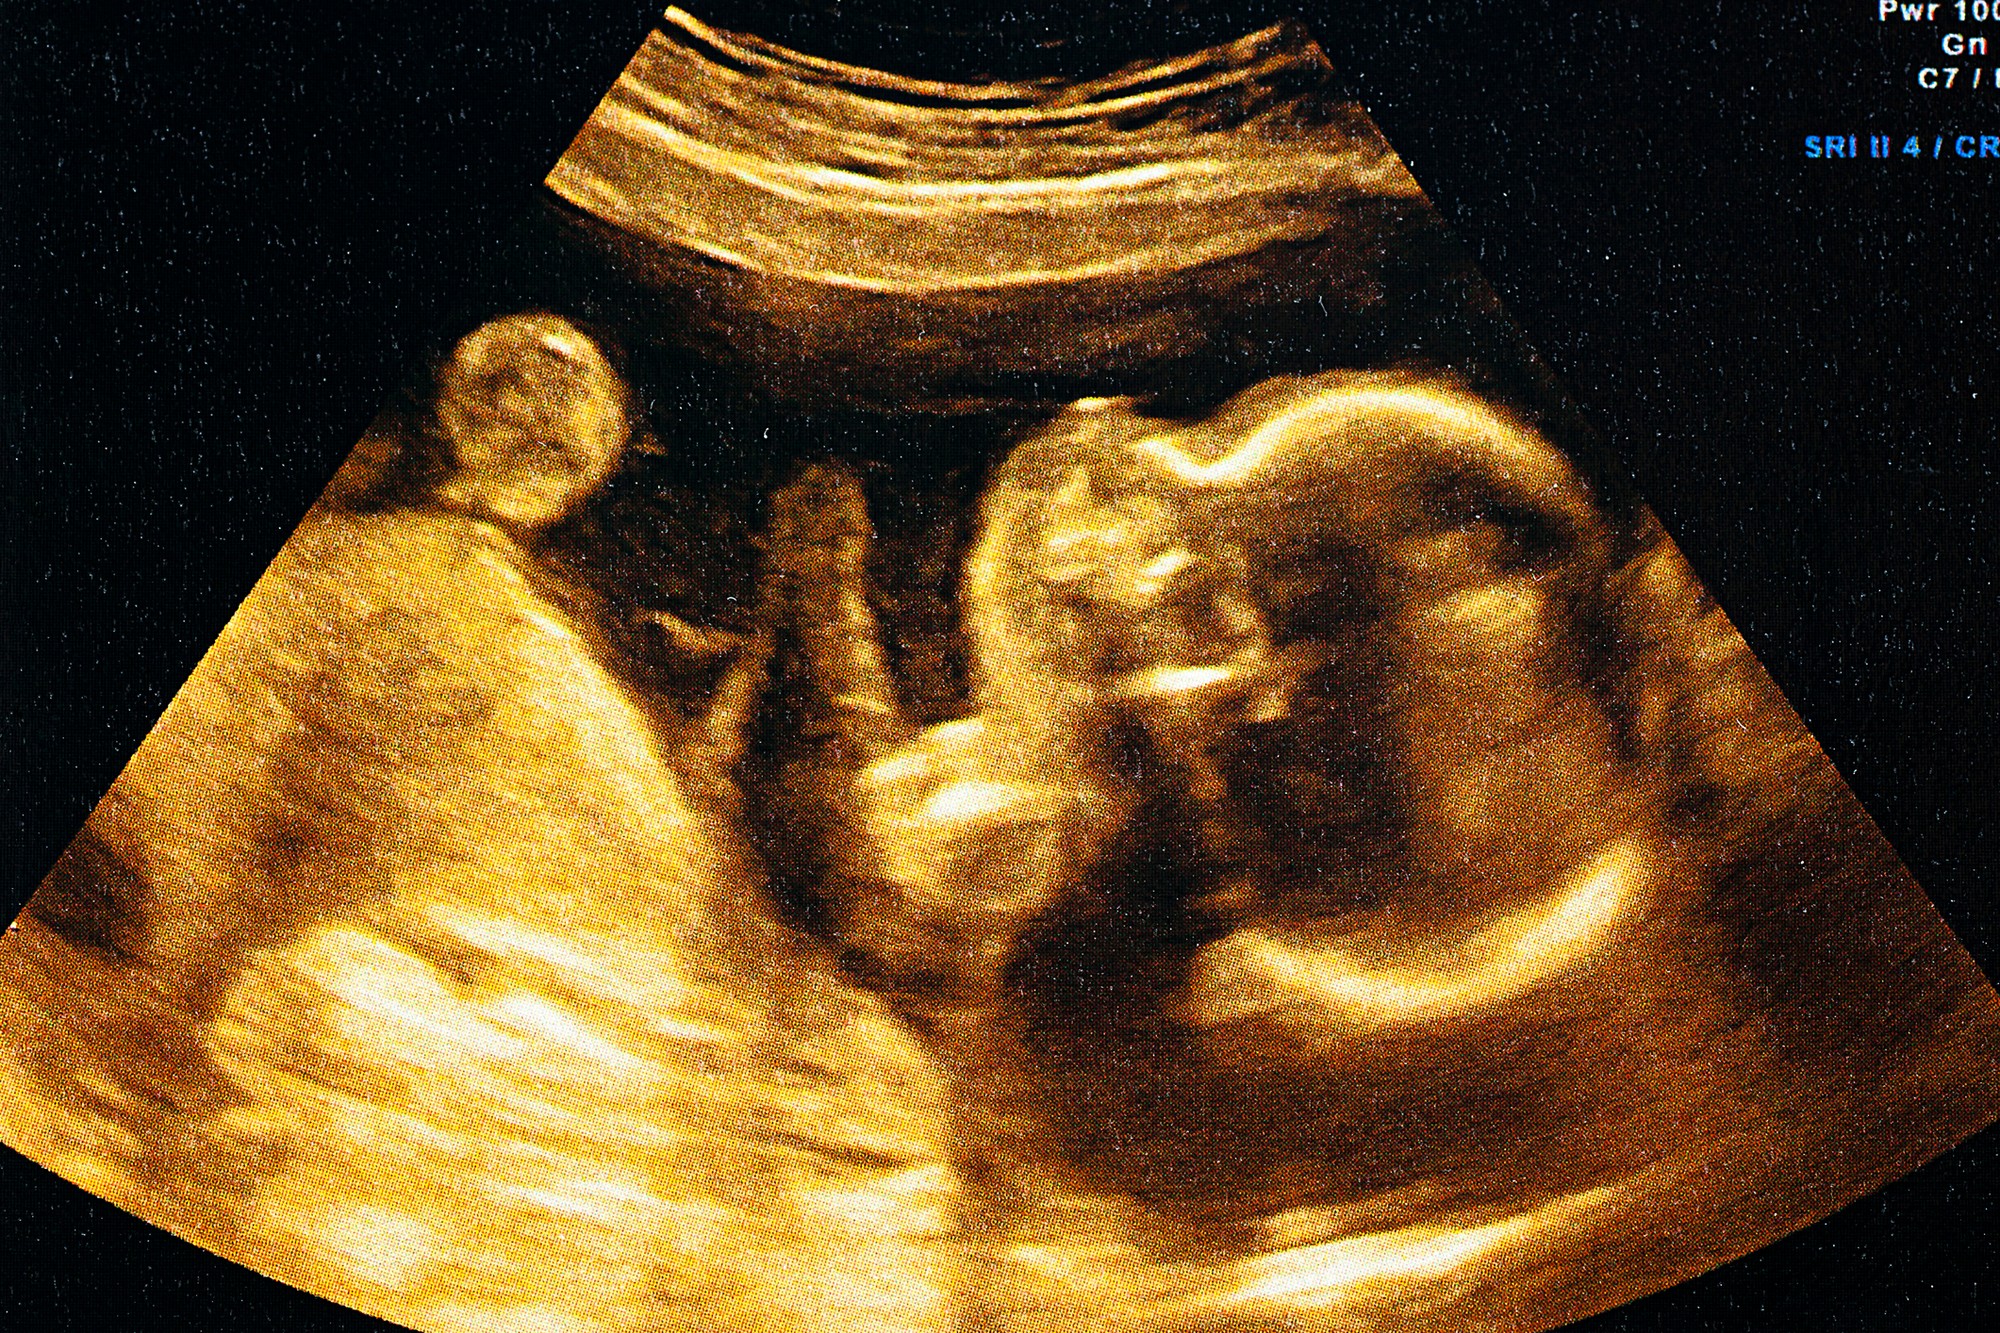

Lekári v Bostone nedávno vykonali chirurgický zákrok, ktorý sa zapíše do histórie zdravotníctva. Operáciou mozgu totiž dokázali zachrániť dieťa, ktoré sa nachádzalo v bruchu matky. Ako informoval portál Unilad, zákrok by mal podľa zdravotníkov spustiť revolúciu v liečení choroby zvanej malformácia Galenovej žily.

Počas operácie, o ktorej informoval časopis Journal of NeuroInterventional Surgery, tím 10 zdravotníckych pracovníkov použil dlhú ihlu na vstreknutie látky do cievy v mozgu dieťaťa, aby prinútil krv prúdiť späť. Samotná matka pritom bola v 34. týždni tehotenstva. "Pri každej operácii plodu tu sú dvaja pacienti. Musíte sa uistiť, že je všetko v dokonalom súlade, pretože bez presnej komunikácie a tímovej práce všetkých zúčastnených by sme nič nedokázali," poznamenala doktorka Carol Benson.